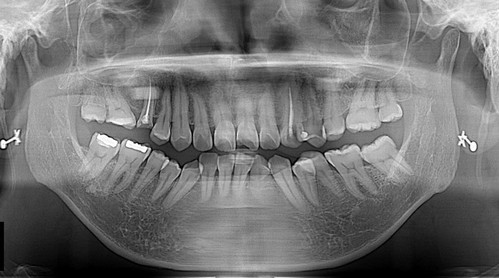

역시 스켈링도 못 받으셨던것 같다.. 약이 들어가고 주무시기 시작해서야 겨우 구강 상태를 살필 수 있었다..

발치가 필요한 치아, 심한 충치가 있는 치아, 치료가 마무리 되지 못한 치아..

대부분 구역 반사가 심하신 분들도 수면치료 준에는 괜찮으신데 이 환자분은 수면 중에도 구역 반사를 간간히 보여서 어시스트와 나 모두 긴장 또 긴장 상태로 진료의 중단과 시작을 반복하면서 첫 날은 스켈링과 아픈치아 발치를 마쳤다...